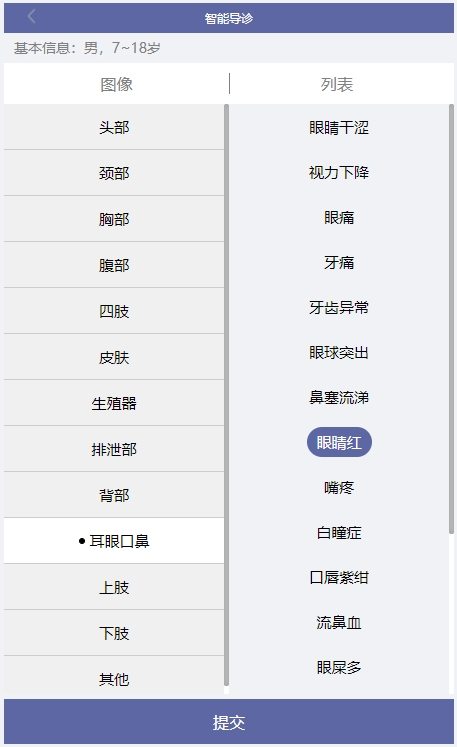

智能导诊界面,可以根据性别来选择人体结构图,有成年男性、成年女性、男童、女童。页面会显示男性或女性的身体结构图,可切换正面/背面。

1、通过点击部位选项,选择自己身体不适的部位,系统会列出该部位的所有症状疾病,患者只需要选择与自己相同的症状,如某些疾病还有需要再确定的地方,患者再次选择相对应的选项,通过智慧导诊系统多维度计算,根据情况提供相关建议,最终推荐就诊的科室。